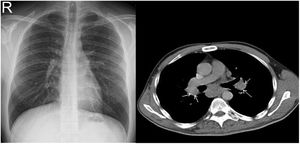

ResultsAmong 109 patients, eighty-one patients CXR and CT imaging taken at the same radiology center has been reached. Demographic, radiological, and clinical data of 81 patients were obtained from a total of 109 patients, and the record data of these 81 patients were evaluated. Patients who could not be reached for all tests were excluded from the study. Among 81 sarcoidosis patients 23 (28.4%) were male, 58 (71.6%) were female. The mean patients age was 46.4 years and the mean disease duration was 3.8 years (Table 1). As for system and organ involvement; arthritis was seen in 62 (76.5%), Löfgren's syndrome in 13 (16%), erythema nodosum in 32 (39.5%) patients, uveitis in 10 (12.3%) patients, myositis in 1 (1.2%) patient, and neurosarcoidosis in 1 (1.2%) patient. In laboratory tests, increased serum levels of angiotensin-converting enzyme (ACE) were detected in 42 (51.8%) patients, serum calcium in 7 (8.6%) patients, and serum vitamin D3 in 1 (1.2%) patient. As for the acute phase reactants, increased C-reactive protein (CRP) level was detected in 38 (46.9%) patients and increased erythrocyte sedimentation rate (ESR) in 41 (50.6%) patients. Among 81 patients, CXR is regarded as normal at diagnosis in 30 (37%) patients, while all of these patients had findings consistent with sarcoidosis on CT imaging. Eighty-one patients which have findings consistent with sarcoidosis on CT examination were as follows: stage 1 (bilateral hilar lymphadenopathy) in 52 (64.2%) patients, stage 2 (bilateral hilar lymphadenopathy+pulmonary infiltrate) in 20 (24.6%) patients, stage 3 (only pulmonary infiltrate without hilar lymphadenopathy) in 6 (7.4%) patients, and stage 4 (pulmonary fibrosis) in 3 (3.7%) patients with sarcoidosis (Table 2). Regarding disease stages, CT imaging detected more patients with stage 1 and stage 2, compared with other stages of disease (p=0.02, p=0.04 respectively) (Table 3). When compared with CXR, CT imaging was more superior in the detection of early diagnosis and stage determination of sarcoidosis (p=0.001). One patient had pleural involvement and another one had suspected pulmonary hypertension (PH) detected on CT imaging while CXR was normal in these patients both. CT imaging was more superior for early detection of disease extent and complications, such as pleural involvement, PH, micronodules and active alveolitis. The most frequent findings detected on CT examination were bilateral symmetrical hilar and mediastinal lymphadenopathy, micro and macronodules, located along bronchovascular bundles, interlobular septi, interlobar fissures, and in the subpleural region. In patients with stage 4 the features of alveolitis/fibrosis including “ground-glass” and “honeycombing”, architectural distortion, and traction bronchiectasis were seen. Most frequently, lesions in sarcoidosis demonstrate predilection to the upper and middle fields. There were not found correlation between CT findings and lung function tests (p=0.45).

CXR-based staging of sarcoidosis was developed before the introduction of CT, and for decades, it has been the gold standard for staging, follow-up and prognosis of pulmonary sarcoidosis.14 It was preferential method because of low price, low radiation exposure and wide use as well. However, the intensity of symptoms, the presence of extrapulmonary disease, the results of pulmonary function tests, and the necessity of treatment are not well correlated with CXR.15 CXR is insufficient to portray small parenchymal abnormality in early stages of the disease, and small mediastinal and hilar lymphadenopathies. The study showed that there was no correlation between lung function tests (FVC, FEV1 and DLCO) and CXR imaging and it is not a reliable test to detect pulmonary exacerbations of sarcoidosis.16 CT scans are more sensitive than CXR in detecting lung parenchymal changes in sarcoidosis. High-resolution CT (HRCT) can reveal ground-glass opacities, nodules, and peribronchovascular thickening. CT can help in assessing disease extent and severity, guiding treatment decisions, and monitoring disease progression. Unlike X-ray scans, some CT lesions demonstrate a relationship with pulmonary function tests.17 Drent et al. demonstrated correlations between respiratory functional tests and CT features such as thickening of the bronchovascular bundle, intraparenchymal nodules, septal and non-septal lines, or focal pleural thickening.18 Zappala et al. have suggested that compared with CXR presentations, CT scan appear to be more consistent with pulmonary functional changes.19 CT is significantly more sensitive than CXR regarding detection of early sarcoidosis lesions, which may help us for early decision treatment. This is true even in stage 1/2, which is linked with a favorable long-term prognosis. Despite these facts, the predictive significance of CT findings has not yet been subjected to a significant amount of research. Even among chest radiologists, there is considerable heterogenicity and subjectivity in the interpretation of CXR. Baughman et al. evaluated the discrepancy between two chest radiologists initial assessments of Scadding staging using data from a clinical trial.20 Overall, the authors discovered only fair interobserver concordance, and with regards to the presence of fibrosis, they found only fair interobserver concordance. They also mentioned that it was hard to tell if a patient was at stage II or stage III because chest radiologists could not agree on the appearance of hilar lymphadenopathy. Zhang et al. compared the chest CT and CXR imaging for staging of pulmonary sarcoidosis using clinical records of 227 sarcoidosis patients.21 They reported that overall, 50.2% patients showed discordant sarcoidosis stage between CXR and CT, which findings support the results from our present study. The primary reason for inconsistent stage between CXR and HRCT was failure to detect mediastinal lymph node enlargement in the shadow of the heart in CXR and small nodules because of the limited resolution of CXR. Also they found more patients with pleural involvement detected by CT (25.6%) compared with CXR (7.5%). In addition, the authors recommend new staging criteria for pulmonary sarcoidosis according to CT imaging, not CXR. Russo et al. investigate the sensitivity and specificity of different chest imaging for sarcoidosis screening in patients with cardiac presentations.22 While the CXR was suboptimal as a screening test, in contrast CT and cardiac/thorax MRI had excellent sensitivity. CT has the highest specificity among imaging modalities. Sarcoidosis primarily affects the upper lung zones, and granuloma are predominantly spread along lymphatics, it is more difficult to assess these regions using CXR and when assessing lesions of this kind, CT is preferable method. CT may also distinguish confluent granulomas, which have a peculiar imaging result known as the “galaxy sign,” which resembles a star cluster when viewed through a telescope.23 CT also may help in the differential diagnosis of sarcoidosis with lymphangitic carcinomatosis, which can present with a nodular perilymphatic pattern and septal thickening. Various studies have demonstrated the superiority of CT in detecting lesions corresponding to fibrosis and in diagnosing more advanced stages of the disease.24 CXR scans revealed fibrosis in 5–10%, whereas CT scans resulted in such changes being described in as many as 20–50% of patients. In fibrotic stage, the presence of “honeycombing” and traction bronchiectasis is associated with worse prognosis, and a larger degree of fibrotic alterations detected on CT scan is known to be predictive of mortality.25 Our research results align with previous studies in the literature. In this investigation, we observed that CT imaging outperforms CXR in terms of early detection and staging of sarcoidosis (Fig. 1). The predominant stages identified through CT examination, which were not visible on CXR, were stage 1 and stage 2 (Fig. 2). Furthermore, CT imaging provided valuable insights into pleural involvement, early alveolitis, and pulmonary hypertension.25 Nevertheless, our study does have certain limitations. Firstly, the data we used was confined to a single center and involved a relatively small number of patients, which restricts the generalizability of our findings to all sarcoidosis patients. Another limitation is that our study population consisted solely of individuals of Caucasian origin, and it is widely acknowledged that disease phenotypes may exhibit significant racial differences. Consequently, it is essential to replicate our findings in a group of African-Americans to ensure their broader applicability. Furthermore, had we enrolled patients consecutively and conducted a prospective evaluation of CXR and CT scans with a larger number of readers, it would have likely minimized potential biases in the results. Despite these limitations, it is worth noting that our findings align closely with those reported in existing literature on the subject.